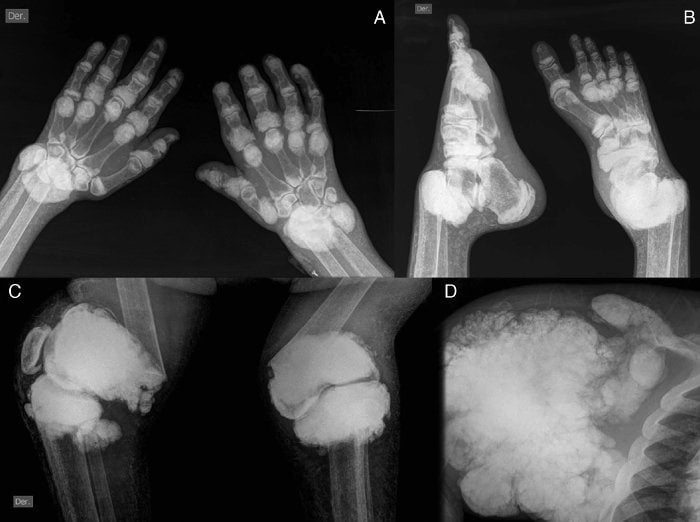

Подагра — ревматическое заболевание, причиной которого становятся тофусы, или кристаллы мочевой кислоты, постепенно накапливающиеся в полости сустава. Клинически патология проявляется рецидивами артрита. Человек страдает от мучительных болей в суставах, их отечности и скованности движений. Постепенно в патологический процесс вовлекаются почки — развивается мочекаменная болезнь. При тяжелом течении подагры у больных диагностируется почечная недостаточность. Нарушается мочевыделение, усиливаются отеки из-за задержки жидкости в организме.